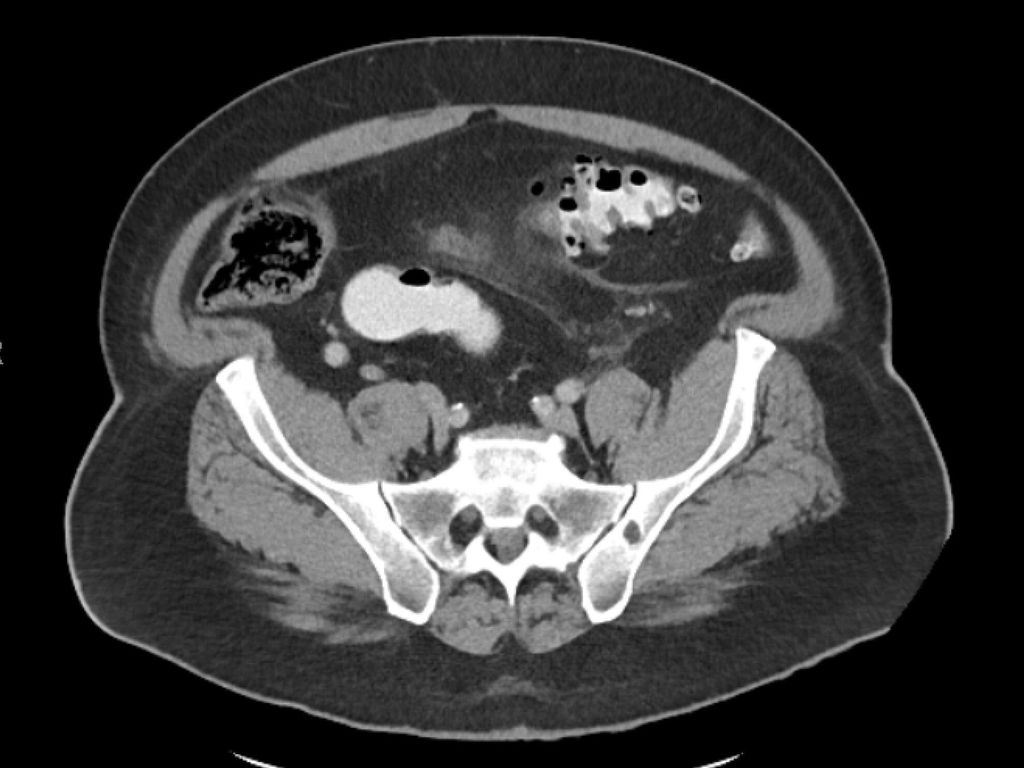

diverticulite compliquée aiguë (type 2a–c) (Fig. 2 et 3) et

La diverticulite compliquée aiguë de type 2 distingue, avec les types 2a et 2b, la perforation couverte avec micro-abcès (≤3cm) et macro-abcès (>3cm). Le type 2c désigne la perforation libre avec péritonite purulente ou fécale. La diverticulite compliquée aiguë nécessite une hospitalisation et doit être traitée par une antibiothérapie. Si l’apport en liquides est insuffisant, il convient de substituer les liquides par voie parentérale. Un apport alimentaire adapté à la situation peut être mis en place. Contrairement au macro-abcès de type 2b, le micro-abcès de type 2a n’est pas accessible au drainage interventionnel. Si le traitement est efficace, il n’y a pas forcément d’indication d’une opération élective. Il convient de noter que le risque de récidive est corrélé à la taille de l’abcès. Les abcès rétropéritonéaux ou péricoliques (>3cm) peuvent faire l’objet d’un drainage interventionnel. Après une thérapie conservatrice ou interventionnelle réussie de la diverticulite, une opération peut être proposée dans l’intervalle sans inflammation, après environ 6 semaines.

Pour la classification de la diverticulite sigmoïdienne, la «Classification of Diverticular Disease» (CDD) s’est imposée (Tab. 1). Celle-ci a pour but de recueillir les différentes évolutions indépendamment d’une opération ainsi que de stratifier les différents pronostics et options thérapeutiques lors du premier diagnostic ou en cas de récidive. Une distinction est faite entre les formes suivantes: